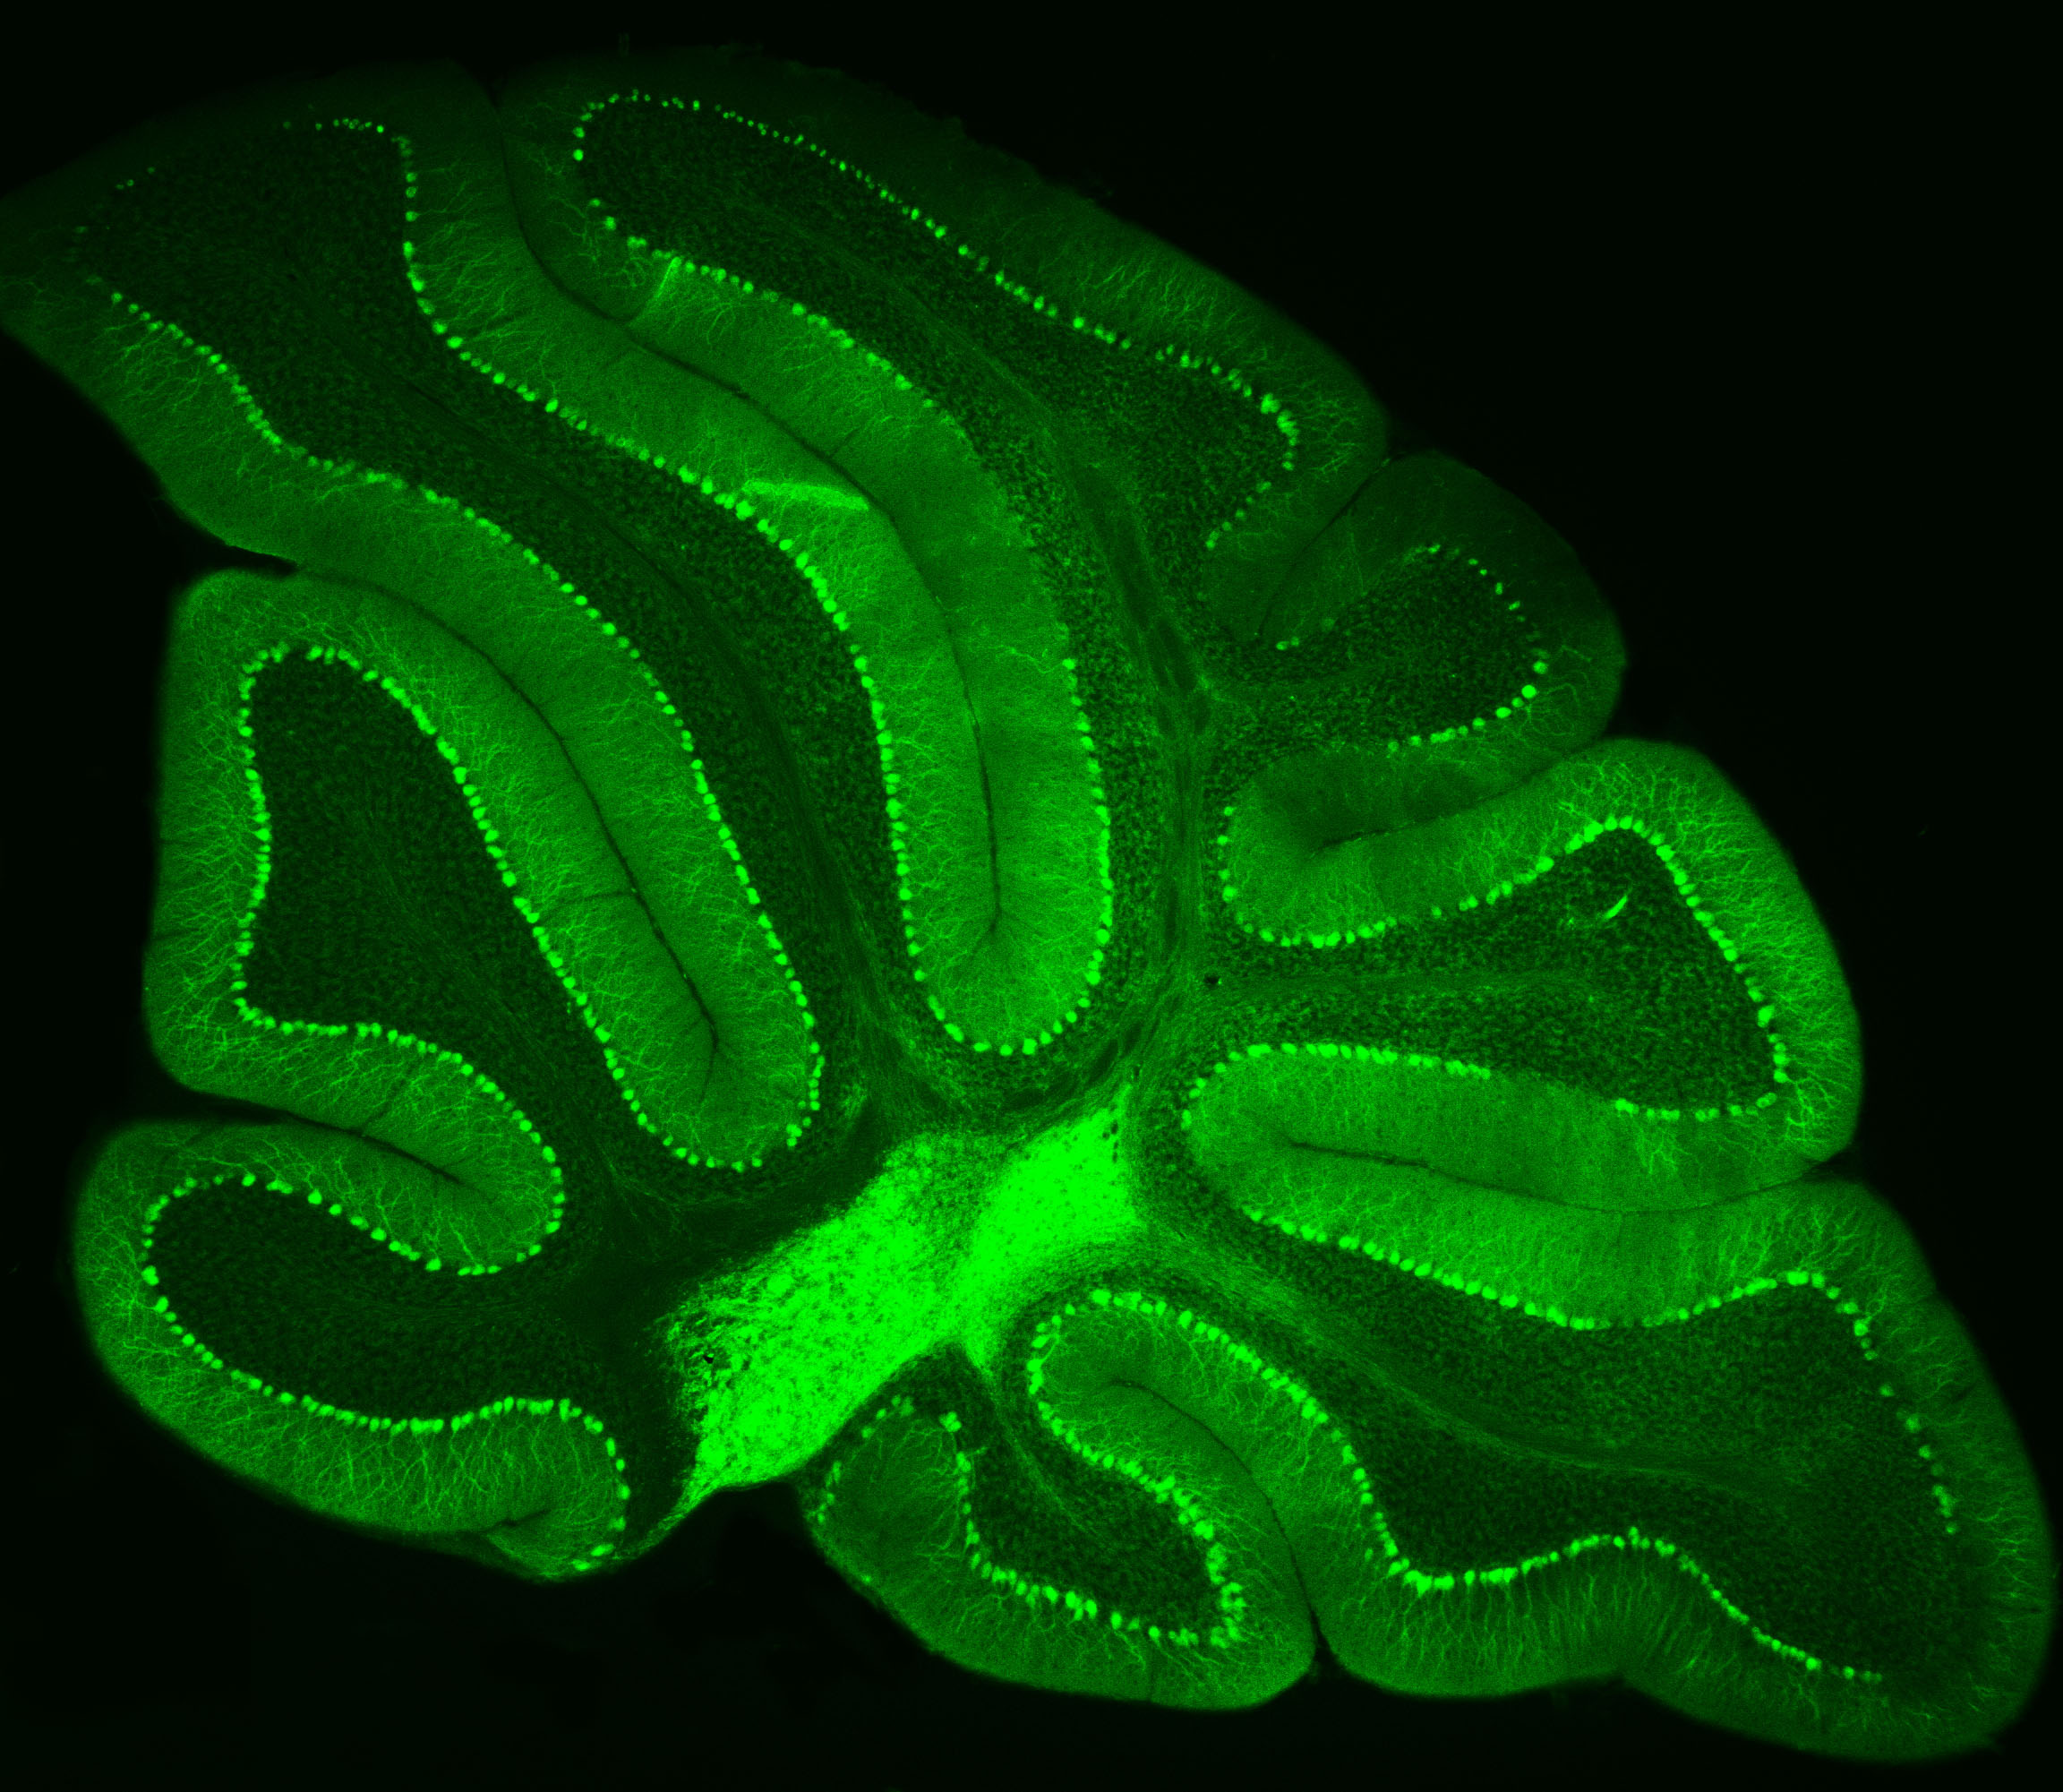

Neurons in Green

Purkinje neurons from an animal model are labeled with green fluorescent protein (GFP), which causes them to glow bright green. Credit: Pennington Biomedical

At Pennington Biomedical Research Center, scientists often study the brain by highlighting specific cells so they can be seen more clearly under a microscope. This technique was recently used by Dr. Yanlin He, associate professor and director of the Brain Glycemic and Metabolism Control Laboratory, who is examining Purkinje neurons in the cerebellum.

Purkinje neurons are best known for helping control movement and motor learning, but researchers are discovering they may have other important roles in the body as well, such as controlling energy balance and blood sugar.

By making these neurons glow green, Dr. He and his team can see their complex branching shapes and how they connect within the cerebellum’s neural network.

This technique also allows researchers to perform electrophysiology recordings, which measure the electrical activity of the cells in a laboratory setting. Their work could help scientists better understand how the brain helps regulate metabolism and overall health.